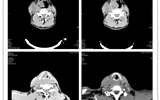

兰大二院耳鼻咽喉科、口腔科联合实施一例高难度、复杂手术